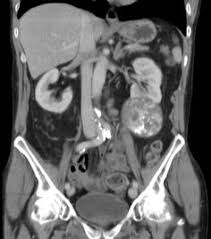

Contrast Enhanced Ct Scan Taken At Two Levels Through The Kidneys A Download Scientific Diagram